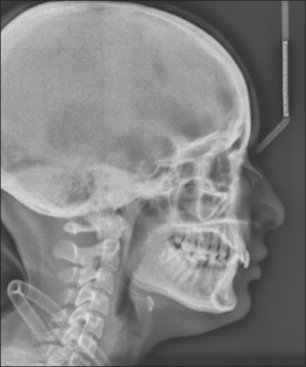

This case report details the treatment of a 23-year-old female patient with Class II division 2 malocclusion with a Class II skeletal base due to a retrognathic mandible. The condition was further complicated by a complete overbite, absence of tooth #36, and a gummy smile. The Forsus appliance has shown to be effective in correcting Class II malocclusion in adult patients, with significant improvements in bite and facial esthetics. The use of temporary anchorage devices for intrusion resulted in lower overbite and increased actual intrusion compared with alternative methods for intruding upper incisors.